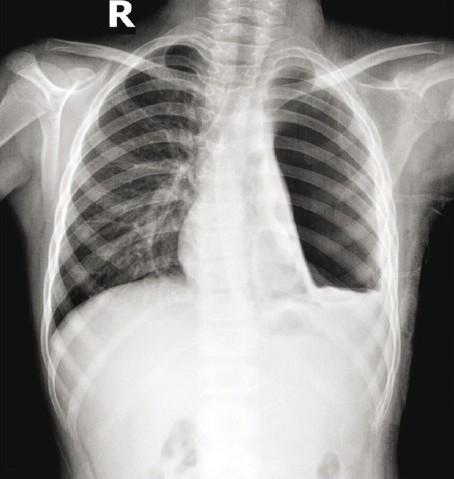

Joshi Jyotsna M

Department of Respiratory Medicine, T. N. Medical College and B. Y. L. Nair Hospital, Mumbai, India.

Lung India. 2011 Oct;28(4):315-6. doi: 10.4103/0970-2113.85745.